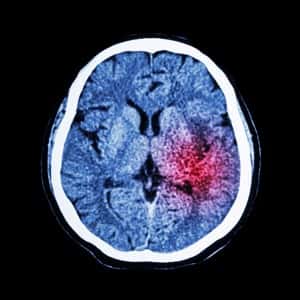

Researchers report counter-intuitive results from a trial on treating hemorrhagic (bleeding) strokes. Usually strokes caused by clots are treated with drugs that can break up clots; strokes caused by bleeding in the brain are not treated with those medications because they could make the situation much worse. While hemorrhagic strokes are less common than ischemic strokes, they are often more devastating.

The phase 3 trial tested the use of alteplase, also known as tPA, a clot-dissolving compound. It was administered to patients with bleeding into the ventricles of the brain. These ventricles normally contain cerebrospinal fluid.

Getting tPA directly into the ventricles in a timely manner reduced death rates by 10 percent and reduced the disability of survivors. In this study the tPA was delivered to the brain ventricles through catheters that had to be placed very carefully so the drug would reach the right part of the brain.